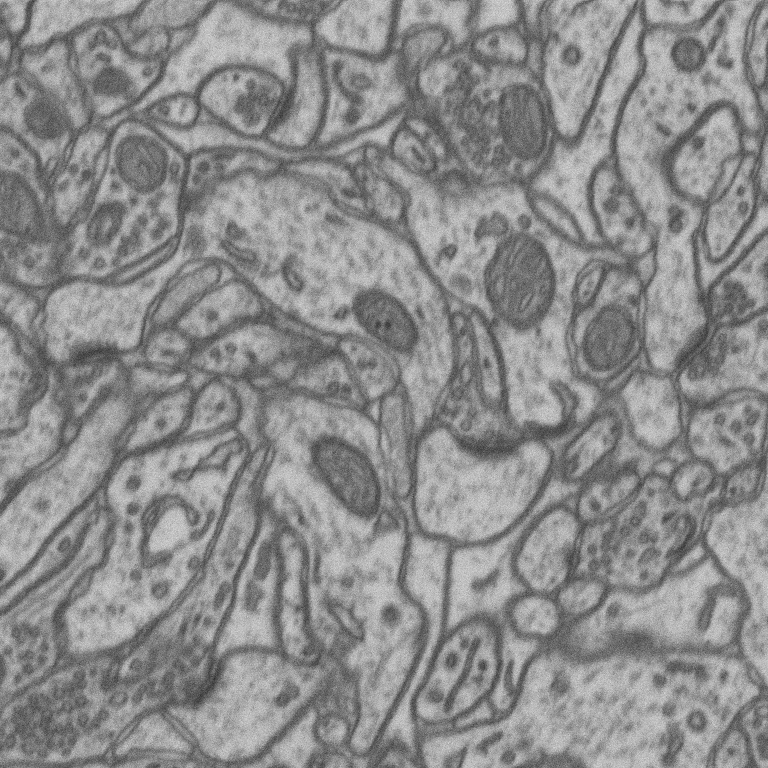

3 Datasets

To analyze the effect of saliency asymmetry in 2D+ representations, experiments were conducted using three datasets: SNEMI, Lucchi, and PA66. Each dataset is composed of grayscale images, which were structured into three-channel representations by stacking temporally or spatially adjacent slices, following a 2D+ approach. Through this setup, spatial continuity was enabled to be captured by the models, while the distribution of saliency across channels was investigated. Figure 2 presents a raw image and its corresponding mask for each dataset.

Refer to caption

(a) SNEMI raw

(b) Lucchi raw

(c) PA66 raw

(d) SNEMI mask

(e) Lucchi mask

(f) PA66 mask

Figure 2: Example images from the three different datasets used in the study. The top row contains raw input images, while the bottom row shows their corresponding segmentation masks.

3.1 SNEMI dataset

The SNEMI dataset contains high-resolution serial-section electron microscopy images of brain tissue, commonly used for neural circuit reconstruction. The grayscale slices depict intricate neural structures such as membranes and synapses, with detailed ground truth annotations available for benchmarking segmentation performance [19, 23, 13, 14].

3.2 Lucchi dataset

The Lucchi dataset focuses on mitochondrial segmentation in brain tissue, presenting anisotropic electron microscopy images with complex cellular environments. The fine-grained grayscale images pose a challenge for feature extraction due to subtle boundaries and variable contrast, making it a valuable test case for assessing biases in pretrained color channel weights.